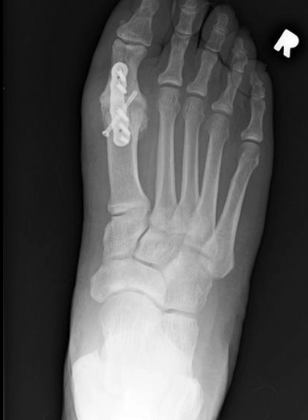

1st MTP fusion involves removing damaged cartilage from the big toe joint and positioning the bones in optimal alignment. The joint is then stabilized using plates and screws to allow the bones to fuse into a single, solid unit.